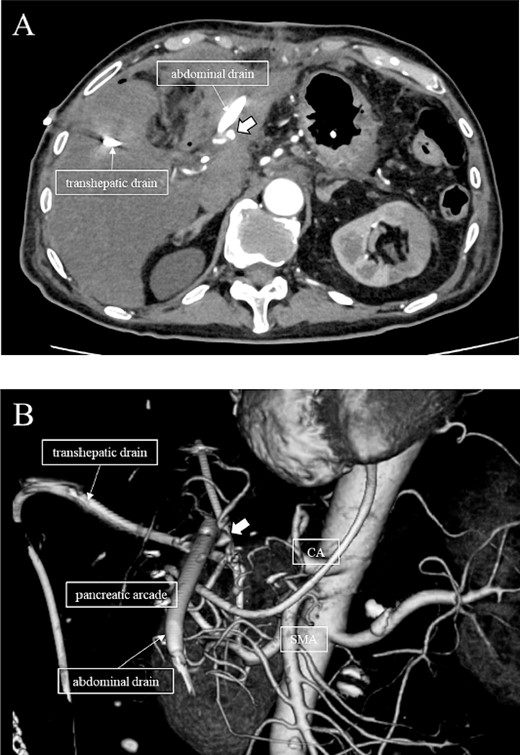

A 76-year-old man underwent DP-CAR after eight courses of gemcitabine and nab-paclitaxel therapy as preoperative chemotherapy for pancreatic body cancer with celiac artery invasion (Fig. 1). As the celiac axis had not invaded into the bifurcation of the left gastric artery, a modified DP-CAR (left gastric-preserving) was performed. Although post operative pancreatic fistula (POPF) developed on postoperative Day (POD) 5, and biliary fistula developed on POD 17. Bile leak was thought to be caused by the rupture of the choledochal duct due to bile duct ischemia caused by CHA transection. Subsequently, both the POPF and biliary fistulae were drained and fistulated. However, on POD 47, the drainage fluid became bloody. Contrast-enhanced computed tomography (CeCT) revealed a pseudoaneurysm at the junction of the gastroduodenal artery (GDA) and proper hepatic artery (PHA) (Fig. 2A and B).

(A, B) CT on postoperative day 48. Contrast-enhanced CT showing a pseudoaneurysm at junction of the GDA and PHA (arrow).

Subsequently, interventional radiology (IVR) was performed. However, because the inferior pancreaticoduodenal artery (IPDA) was very narrow, the microcatheter could not be followed, and hemostasis with IVR was difficult. Therefore, on POD 48, relaparotomy pseudoaneurysm repair was performed. The abdomen was opened through an inverted L-shaped incision, and adhesiolysis was performed, after which a pseudoaneurysm was revealed at the junction of the GDA and PHA. Four transfixing sutures with 3–0 prolene were used. After confirming that the liver blood flow was maintained, surgery was completed. However, bloody drainage from the drain was observed on POD 56. CeCT revealed a pseudoaneurysm (Fig. 3A and B). IVR was considered difficult because of the narrow blood vessels; therefore, the patient underwent a second laparotomy for hemostasis. A pseudoaneurysm was further observed at the junction between the GDA and PHA. In this operation, we used deeper and wider penetrating sutures than in the previous surgery to completely halt blood flow in the GDA. We confirmed that the blood flow to the liver was maintained; however, it was deemed weak. The patient had an uneventful postoperative course without bleeding, and CeCT performed on POD 61 confirmed the disappearance of the pseudoaneurysm. Although the blood flow in the PHA could not be confirmed, the right and left hepatic arteries were preserved (Fig. 4). On POD 76, CT revealed no liver abscesses or infarctions. The drain was removed on POD 78, and the patient was finally discharged on POD 107 without rebleeding or liver failure.

(A, B) CT on postoperative Day 56. Contrast-enhanced CT shows a pseudoaneurysm at junction of the GDA and PHA (arrow).